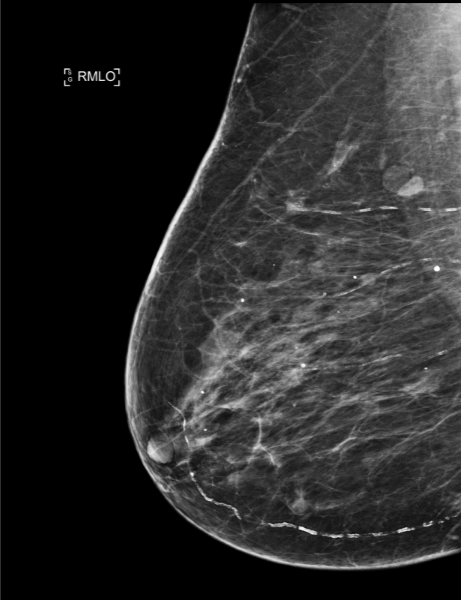

Case of the Week (week 38, 2022)

84-year-old patient, individual screening mammogram.

MammoScreen® points to an increased opacity with slightly irregular contours of the upper external quadrant of the right breast associated with polymorphic microcalcifications.

Ultrasound does not find a biopsy target, a macro biopsy is performed on microcalcifications and intra-ductal carcinoma.

*Case from Dr. Le Van An